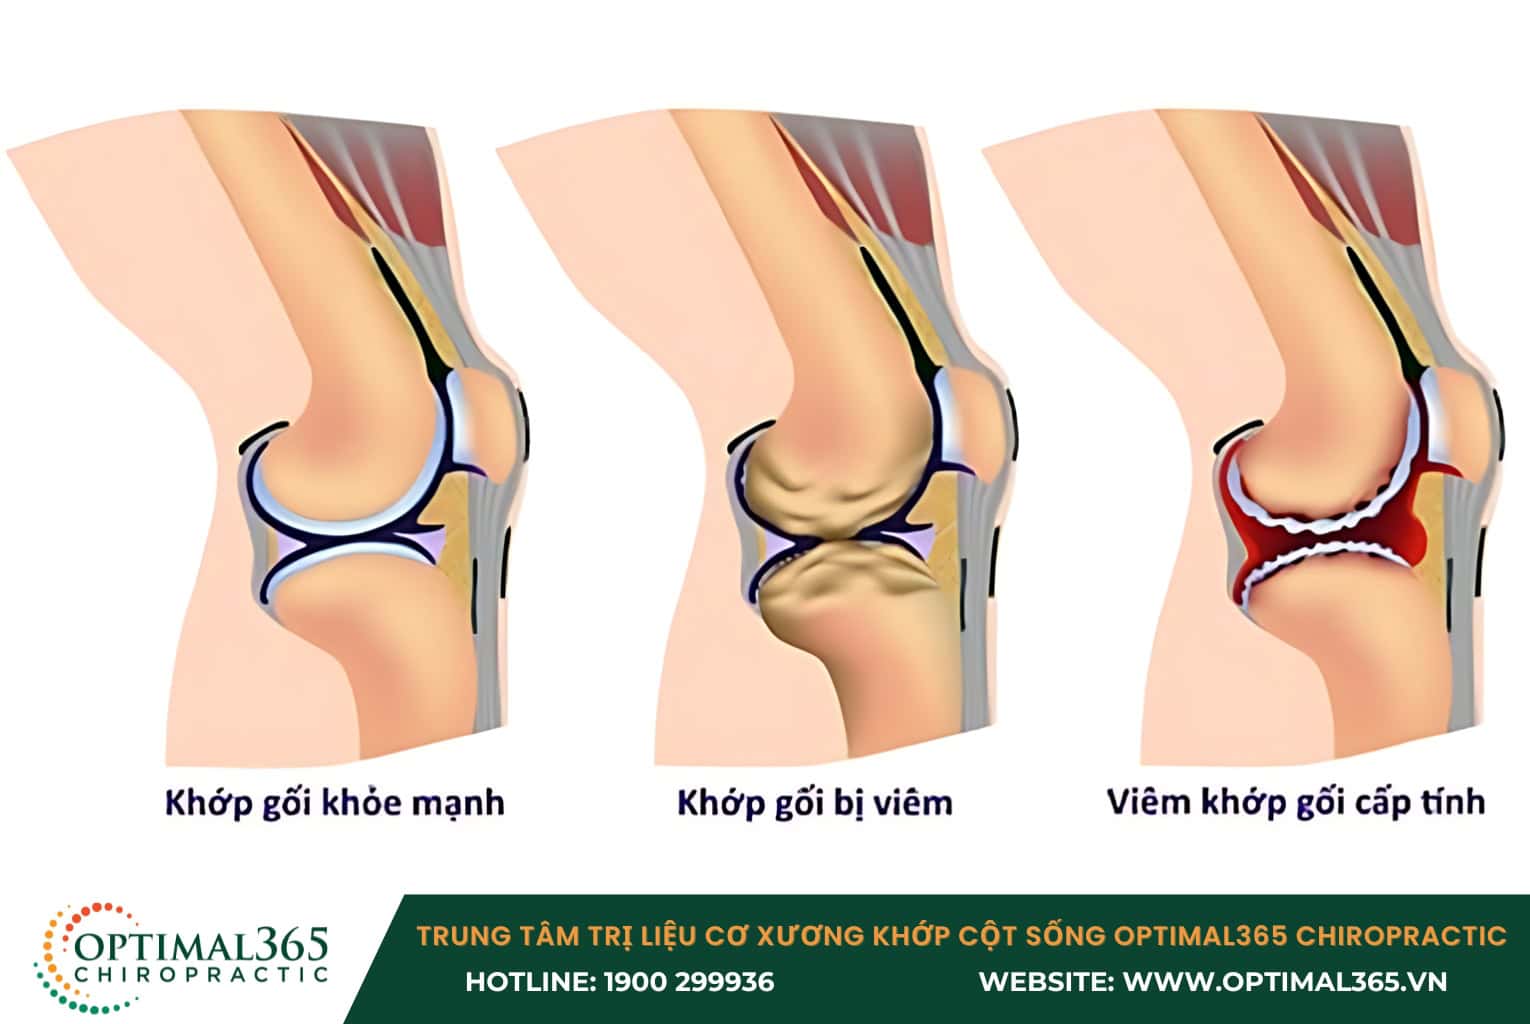

- Thoái hóa khớp sớm: Khi khớp gối mất đi sự ổn định do tổn thương dây chằng kéo dài, sụn khớp phải chịu áp lực lớn hơn, dễ dẫn đến sự mòn và thoái hóa sớm. Thoái hóa này thường xảy ra quanh vùng bánh chè, khoang trong và ngoài của khớp, gây đau và hạn chế cử động.

- Tổn thương sụn chêm: Sụn chêm là lớp đệm giữa các xương khớp gối, và khi dây chằng bị tổn thương, khớp gối mất đi sự ổn định, gây áp lực lên sụn chêm. Điều này có thể dẫn đến rách hoặc biến dạng sụn chêm, tăng ma sát trong khớp, gây đau nhức và làm giảm khả năng vận động.